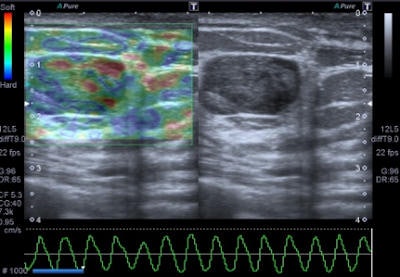

Freehand ultrasound, or compression elastography ("strain elastography"), is based on the application of a compressive force to the breast and on the measurement of the shape-deforming effect, thus providing a value of lesion stiffness compared with that of surrounding tissues, the authors wrote. A slight manual compression/decompression is applied using a conventional transducer, or the deformation may be determined by respiratory movements.

"The technique allows only for qualitative and semiquantitative assessments of a lesion because the force exerted by manual compression is unknown to the equipment, thus allowing only the calculation of the deformability ratio (strain ratio) and not the absolute elasticity," Ricci wrote and colleagues.

Benign lesions are described at elastography as lesions with a low color map score (score 1-2), while the best cut-off point for discriminating benign from malignant masses falling at the 3-4 boundary of color map classification, according to the Ueno-Itoh score system. Cysts often appear as hard and low deformable lesions, commonly represented with a blue pattern at the color map and with a high strain ratio because of their low compressibility.

Elastography is often used in "uncertain" lesions classified as BI-RADS 3 and 4, but it does not change medical protocol in cases of BI-RADS 1, 2, and 5 lesions. The mean elasticity score of color map was significantly higher for malignant lesions than for benign lesions (p < 0.001), usually mainly represented as blue areas in the color map.